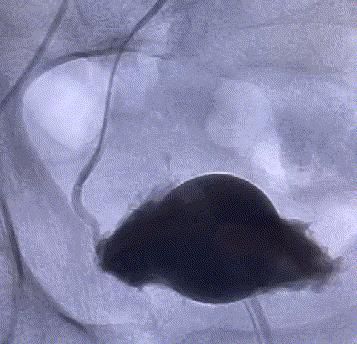

我院這項“很牛”的技術——介入下前列腺動脈超選擇栓塞術,能讓前列腺增生“由大變小”。該技術無須切開任何組織,僅通過股動脈穿刺置入微導管,經動脈的自然腔道,送達前列腺動脈,将PVA材料置于雙側前列腺動脈即可完成手術。其原理是阻斷前列腺營養供給,使其逐漸萎縮變小,從而解除對膀胱、尿道的壓迫,達到治療的目的。

随後,李旭丹主任攜手胡志華主任爲患者實施介入治療,采用改良Seldinger法穿刺股動脈,在DSA引導下經動脈自然腔道,将微導管分别送達雙側髂内動脈進行造影,觀察雙側前列腺動脈分布情況,将微導管超選擇至雙側前列腺動脈,準确置入PVA栓塞材料,成功阻斷前列腺的營養供給,順利完成了治療。